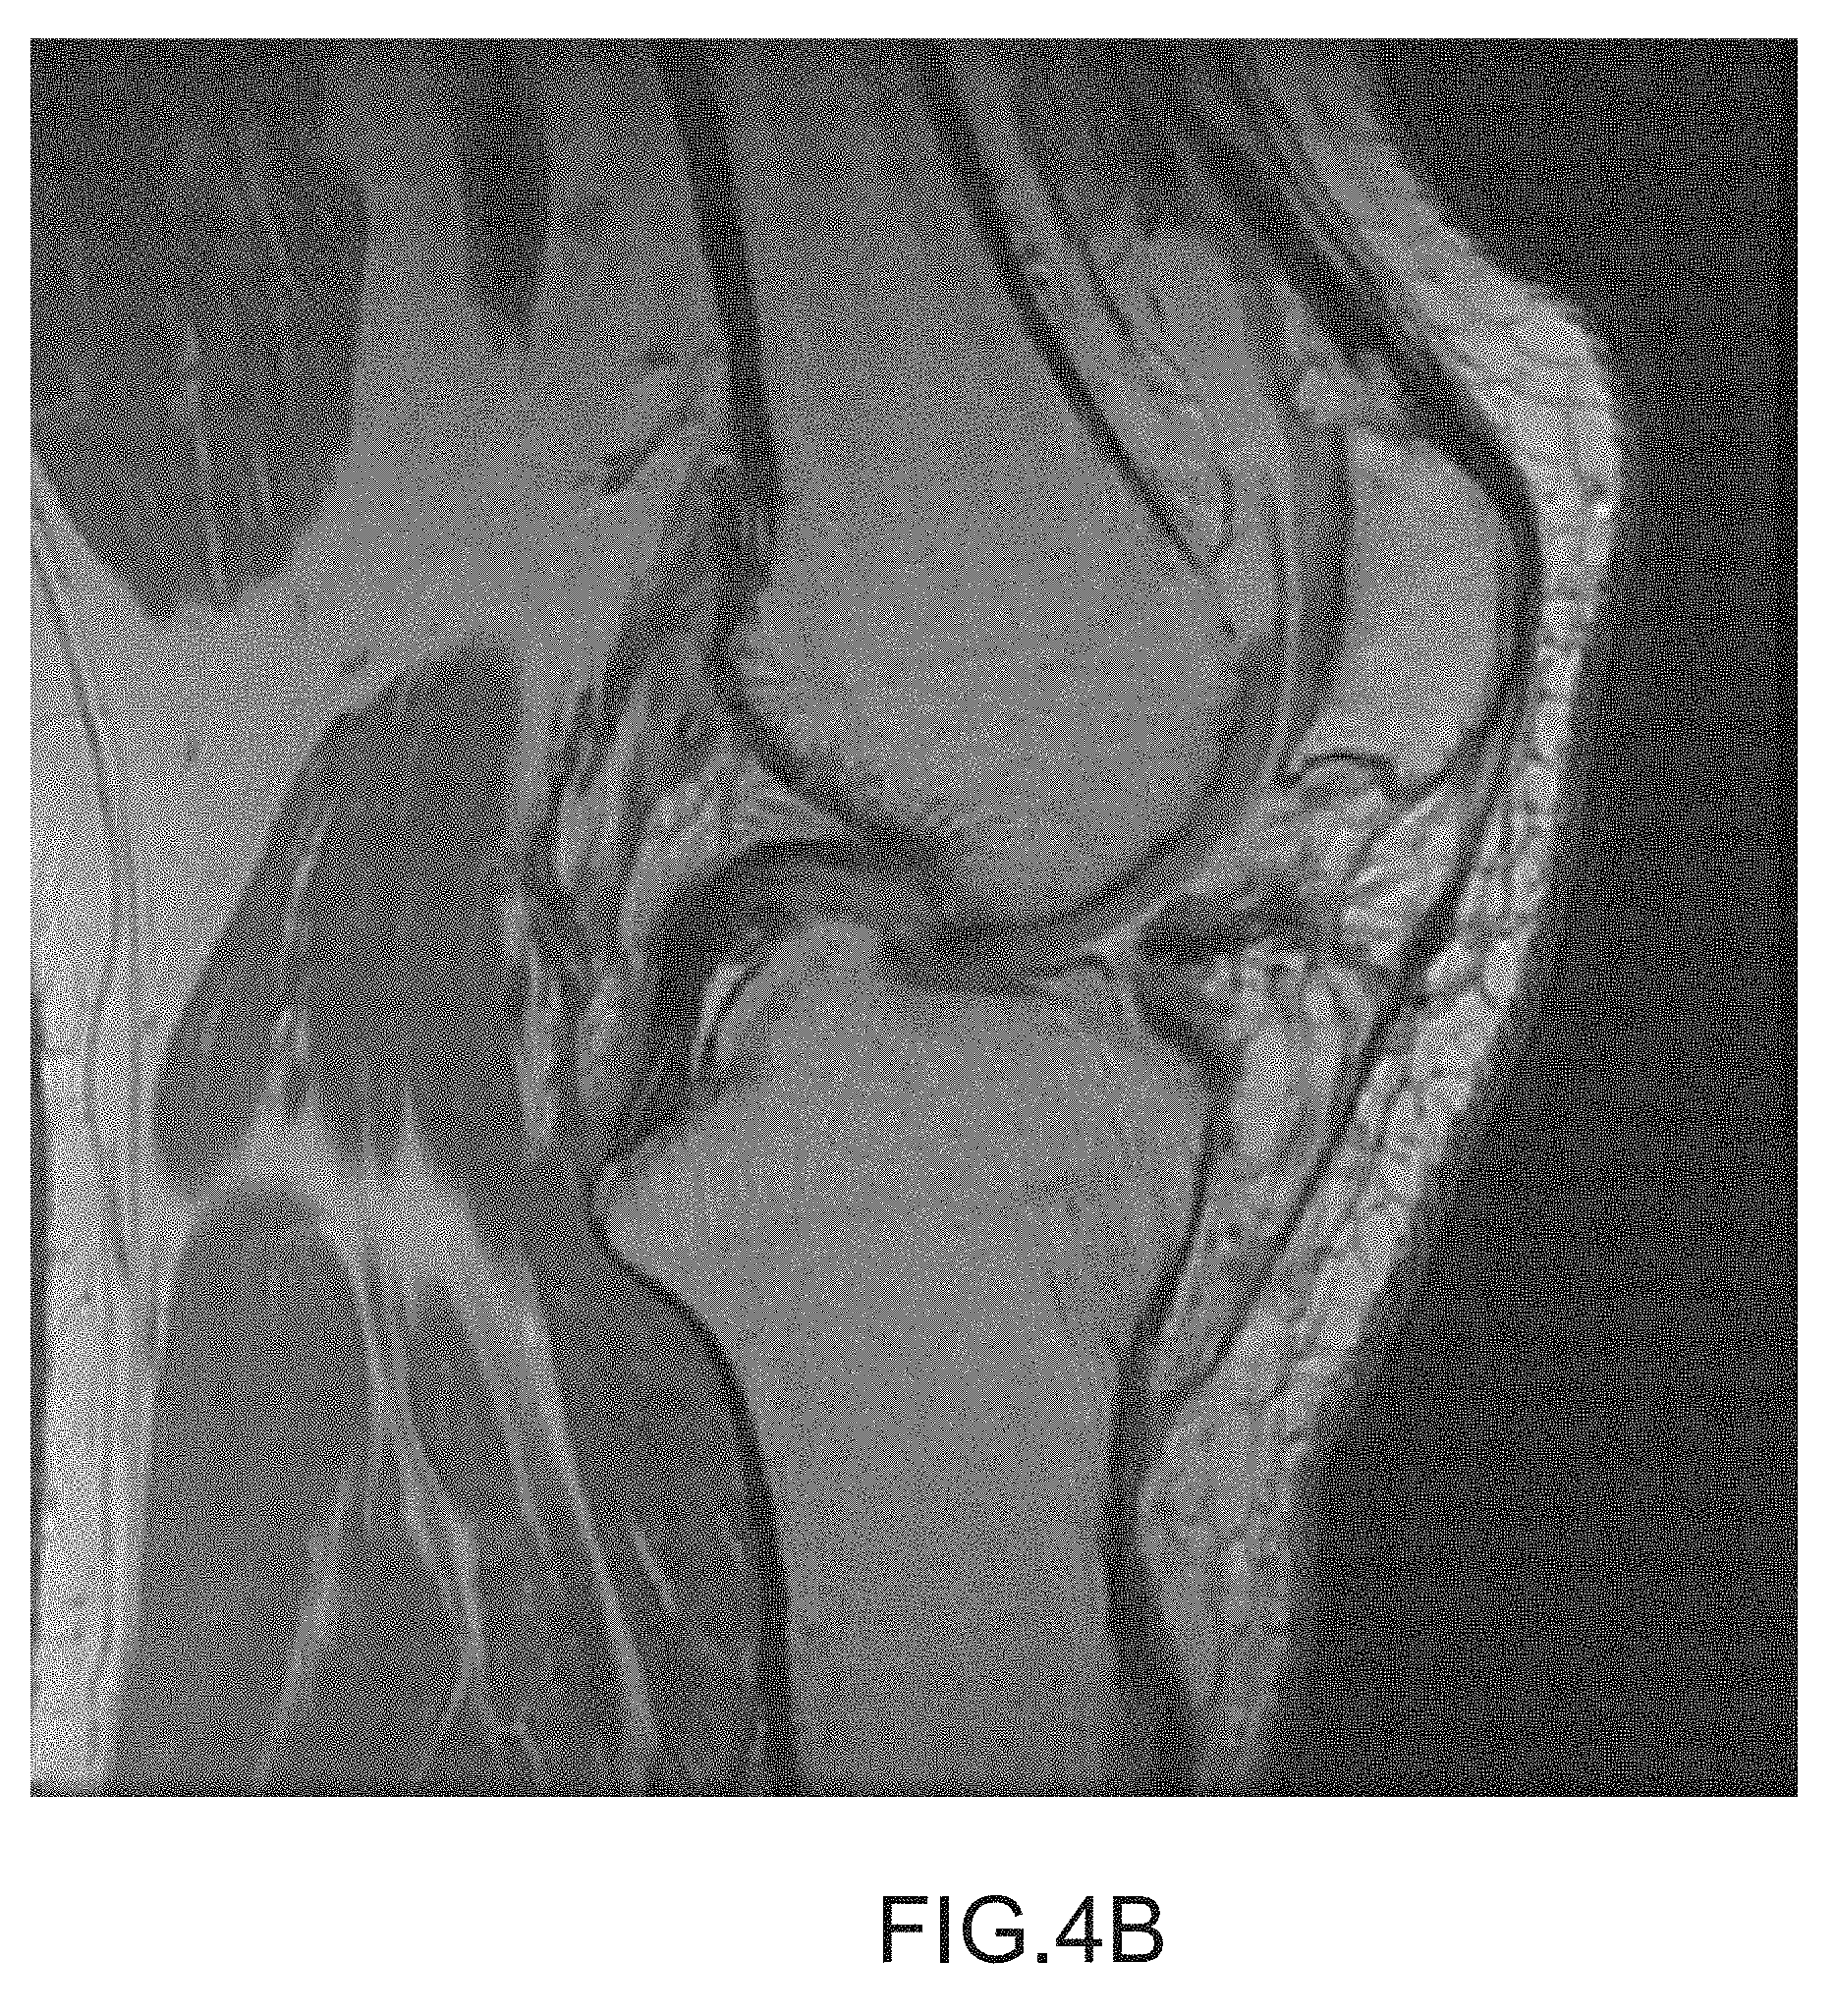

[0047]

FIG. 4B depicts a sagittal plane image slice with a low noise level.

The segmentation method employed by one embodiment may accommodate a variety of intensity gradients across the scan data. FIGS. 3A-C depict intensity gradients (i.e., the intensity varies non-uniformly across the image) in slices (an intensity gradient that is darker on the top and bottom as depicted in FIG. 3A, an intensity gradient that is darker on the bottom as depicted in FIG. 3B, and an intensity gradient 220 that is brighter on the sides as depicted in FIG. 3C) that may be segmented by one embodiment. Further, the embodiment generally does not require approximately constant noise in the slices to be segmented. The embodiment may accommodate different noise levels, e.g., high noise levels as depicted in FIG. 4A as well as low noise levels as depicted in FIG. 4B. The decreased sensitivity to intensity gradients and noise level typically is due to image registration techniques using a golden template, allowing features of interest to be identified even though the feature may include voxels with differing intensities and noise levels.